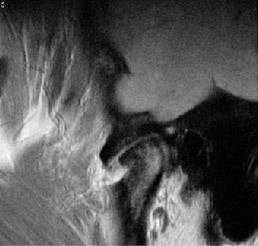

«Застрявший» диск.

«Застрявший» диск. PD sag изображения с открытым (А) и закрытым (Б) ртом - задний край диска (стрелка) остается в нижнечелюстной ямке височной кости. По этой причине открывание рта сильно ограничено. Вероятная причина - образование спаек.